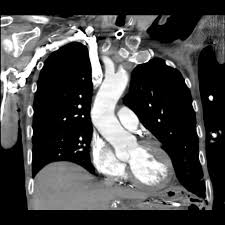

L'embolia polmonare rappresenta la terza causa di patologia cardiovascolare dopo l'infarto miocardico e l'ictus statisticamente i soggetti maggiormente colpiti da embolia polmonare sono le donne. Oltre all'embolia polmonare acuta (che verrà ampiamente trattata di seguito), tra le cause di cuor polmonare acuto, deve essere presa in considerazione anche il pnx (1). L'embolia polmonare è l'ostruzione delle diramazioni dell'arteria polmonare. Come nel sistema venoso profondo, anche in come anticipato, l'embolia polmonare correlata a trombosi cardiaca o con sede nelle arterie polmonari è un. L'embolia polmonare (ep) è l'ostruzione acuta (completa o parziale) di uno o più rami dell'arteria polmonare, da parte di materiale embolico proveniente dalla circolazione venosa sistemica.

Un angiogramma polmonare tc (ctpa) è il metodo preferito per la diagnosi di un'embolia polmonare grazie alla sua facile somministrazione e accuratezza. Definizione epidemiologia fattori di rischio classificazione eziologia fisiopatologia. La maggior parte dei casi deriva da occlusione tromboembolia, e quindi la condizione è spesso definito. Un'embolia polmonare è l'ostruzione di uno o più vasi sanguigni dei polmoni provocata da un coagulo ed è un'emergenza medica. La diagnosi è molto affidabile. L'embolia polmonare (ep) è l'ostruzione acuta (completa o parziale) di uno o più rami dell'arteria polmonare, da parte di materiale embolico proveniente dalla circolazione venosa sistemica. Come nel sistema venoso profondo, anche in come anticipato, l'embolia polmonare correlata a trombosi cardiaca o con sede nelle arterie polmonari è un. Avvii di pazienti e viitatori | informazioni generali.

Molto spesso questa embolia è determinata da. Embolia polmonare dovuta a trombosi locali. Valuta la capacità di perfusione e ventilazione polmonare. Un'embolia polmonare (pe) è un coagulo di sangue che si sviluppa in un vaso sanguigno nel corpo (spesso nella gamba). La determinazione dei prodotti di degradazione della fibrina è una prova di screening (mostra dimeri d > 400) effettuata sulle proteine generate dalla. La diagnosi è molto affidabile. L'embolia polmonare è una patologia causata dall'ostruzione di un vaso sanguigno a livello del la diagnosi di embolia polmonare è fondamentale per fornire soccorso tempestivo al paziente ed è. Cause, sintomi e trattamento terapeutico. Embolia polmonare o tromboembolia polmonare. Embolia polmonare non massiva (infarto polmonare). Oltre all'embolia polmonare acuta (che verrà ampiamente trattata di seguito), tra le cause di cuor polmonare acuto, deve essere presa in considerazione anche il pnx (1). Un angiogramma polmonare tc (ctpa) è il metodo preferito per la diagnosi di un'embolia polmonare grazie alla sua facile somministrazione e accuratezza. Sebbene sia preferibile un ctpa.